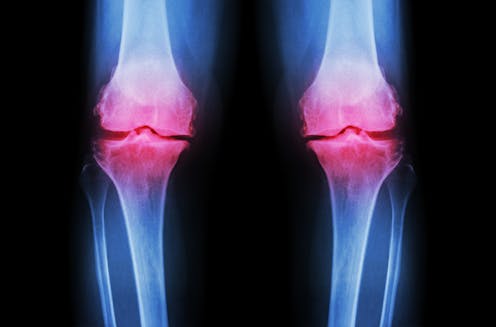

In orthopedics, researchers have proposed using stem cells for the treatment of joint – cartilage damage. This includes osteoarthritis, the thinning of cartilage that causes bones to rub against one another – similar to a car tire going bald after 50,000 miles. Osteoarthritis is the primary cause of joint replacement surgery, and stem cell injections have been promoted as a potential way to avoid joint replacement by regenerating cartilage. Unfortunately, current technology and regulatory issues make obtaining and concentrating true stem cells a challenge, and encouraging them to become and remain cartilage cells and nothing else is even more difficult.

The problem with stem cells is that these cells can continue to evolve; they may not stop development at the cartilage cell phase. They may continue to differentiate into bone cells. This would make the joint even worse because bone creates a rough surface adjacent to the smooth articular cartilage. Bone is actually the end result of arthritis.